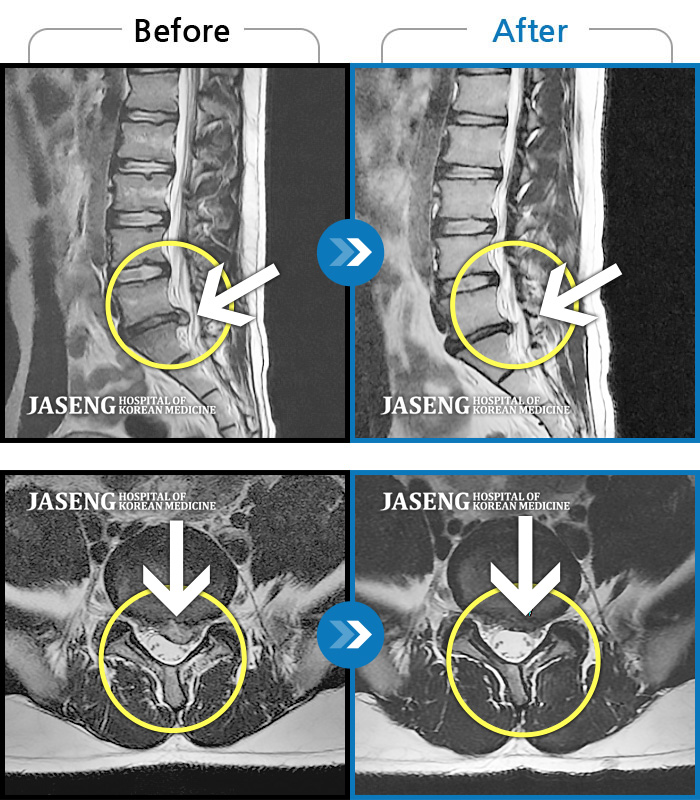

허리디스크

보라매 · 왕오호 원장

허리 통증, 똑바로 서려고 하거나 걸을 때 양쪽 허벅지와 고관절 시큰거림

촬영시기

2017.06.07 ~ 2018.04.17